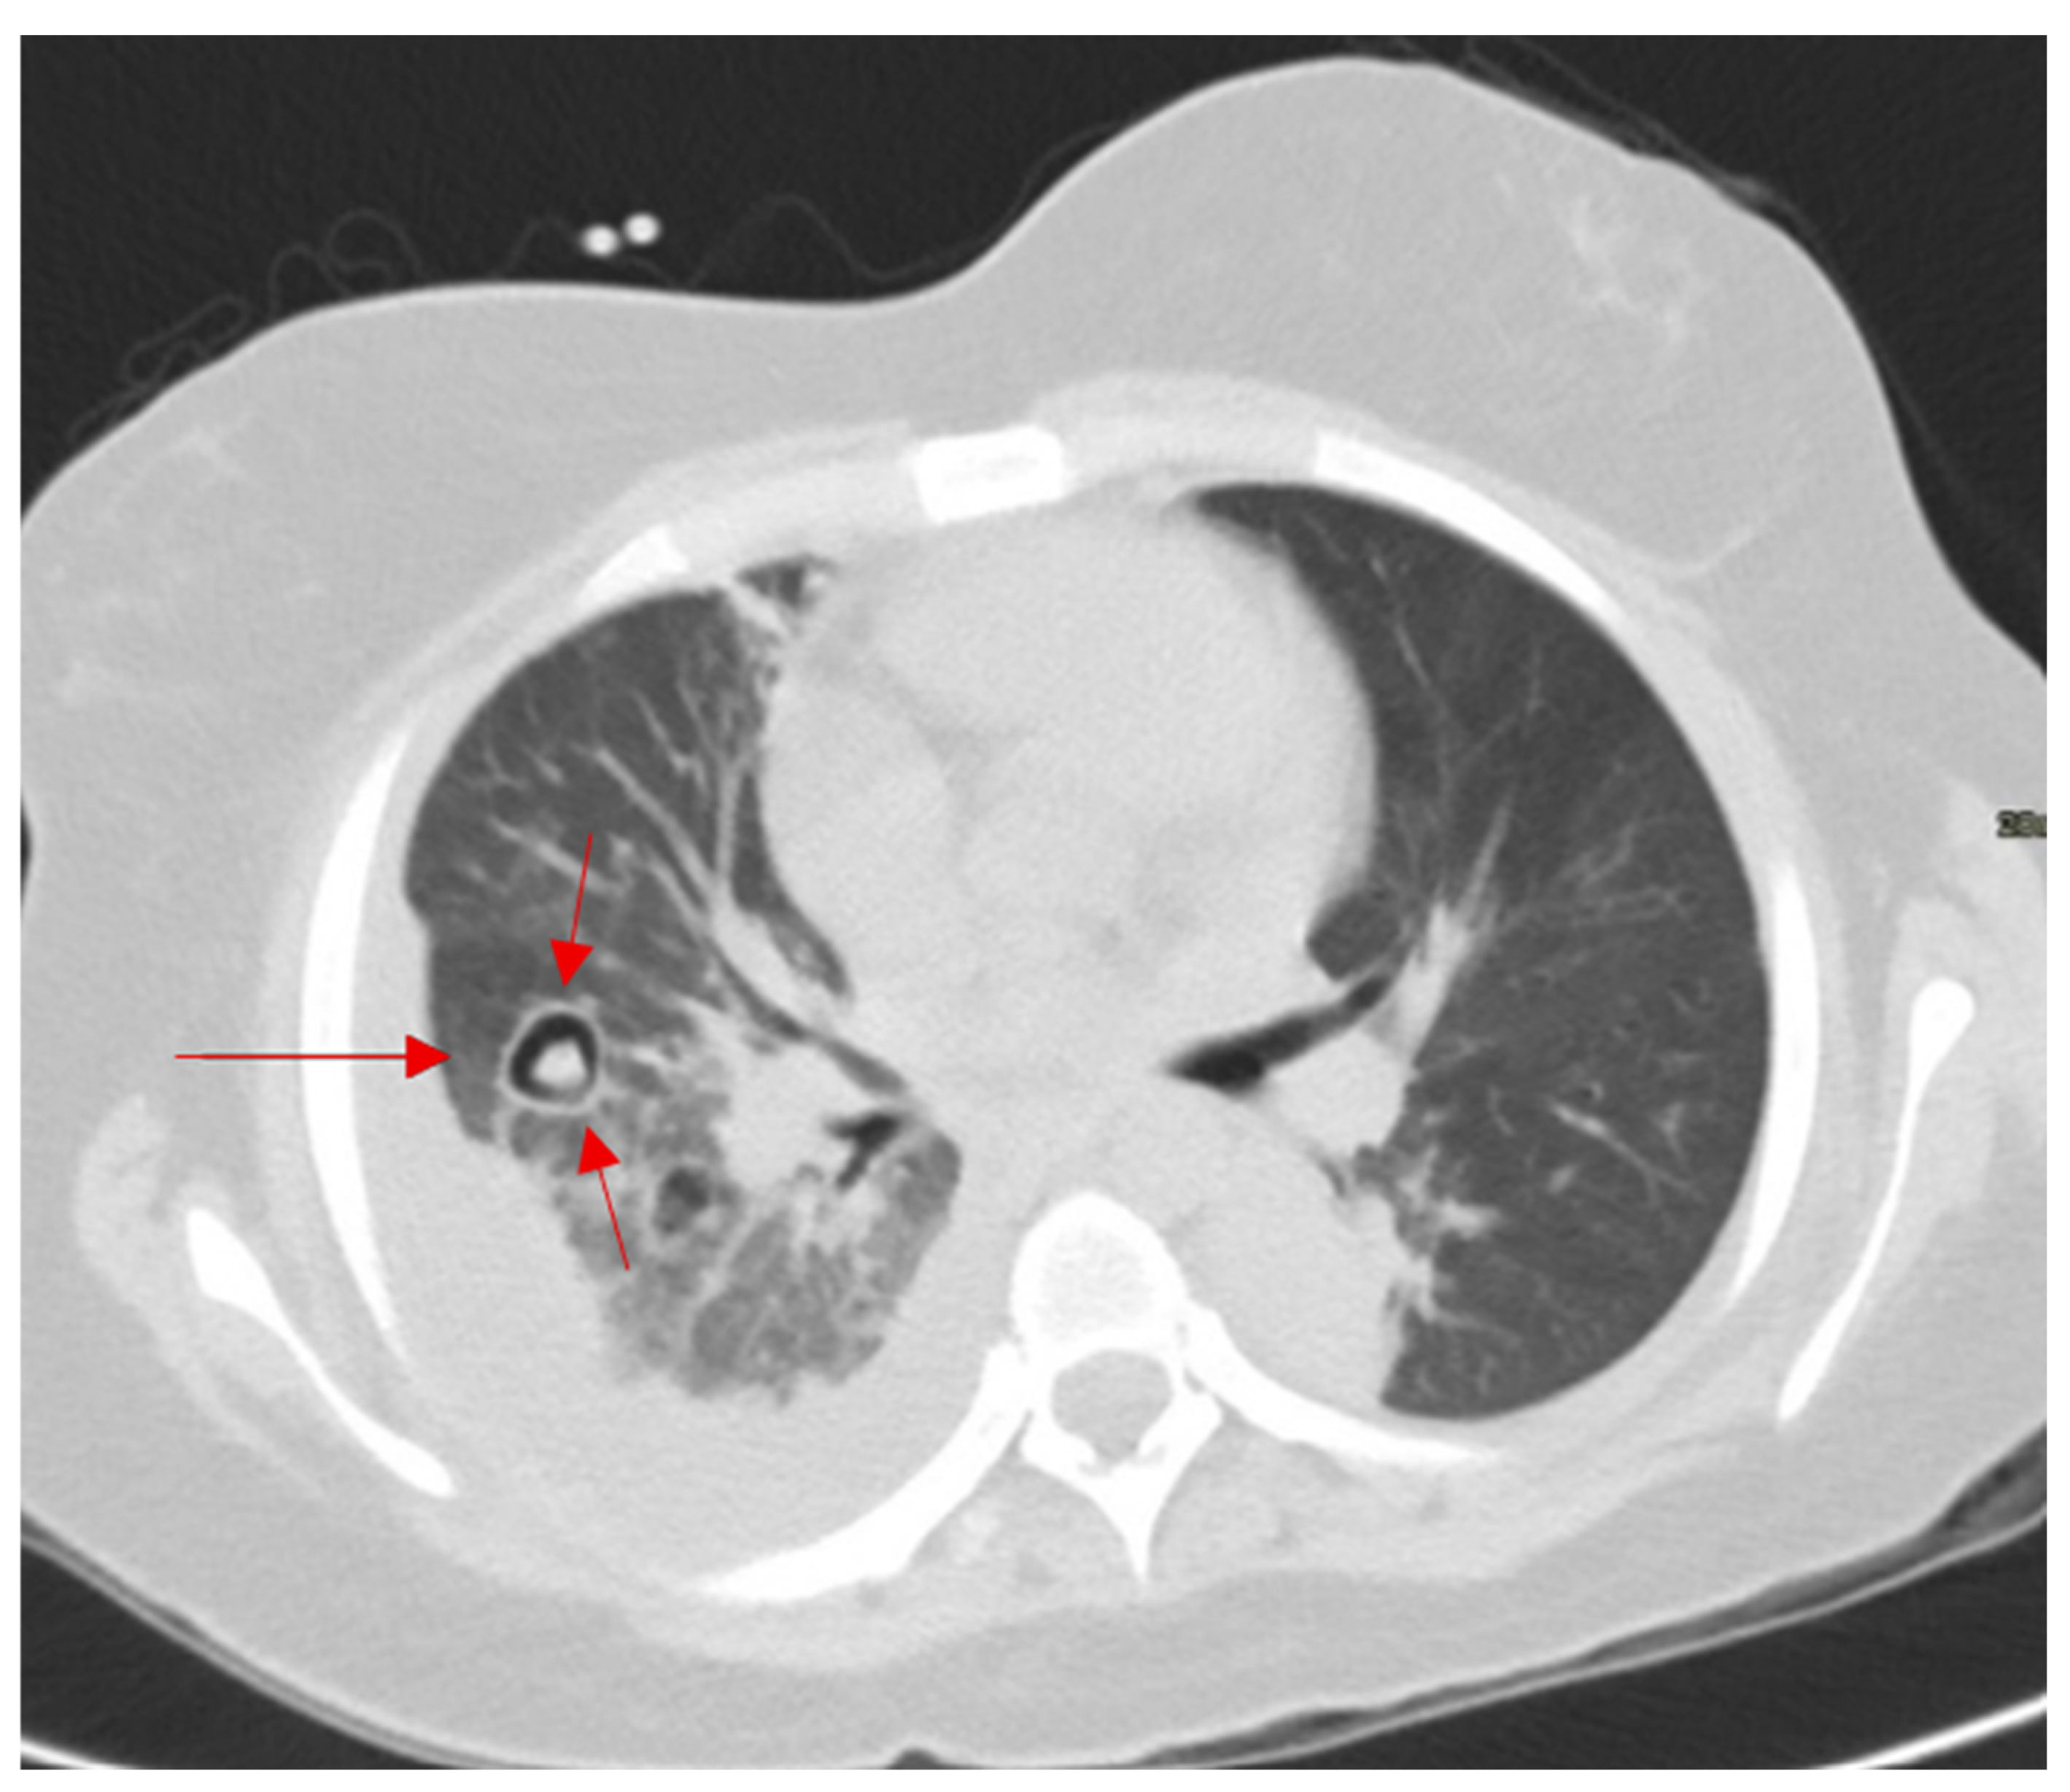

2.14. Air Crescent Sign

In immunocompromised patients with fever, cough, or hemoptysis, an intracavitary air crescent on CT suggests invasive aspergillosis. This sign is one of the delayed signs of invasive pulmonary aspergillosis on conventional chest radiograph or on CT, occurring in approximatively 50% of the patients [65]. It appears encompassed within a pulmonary cavity, and it is the result of the regression of the diseased mass under the effect of neutrophils, indicating bone marrow recovery in immunosuppressed patients (Figure 14) [66]. This finding can also be found in tuberculosis, hydatid cysts, abscesses, carcinomas, and Pneumocystis carinii pneumonia [67,68].

Figure 14.

Axial CT of the chest showing a nodular opacity with retracted infarcted lung and crescentic and circular cavitation in pulmonary aspergillosis (red arrows).